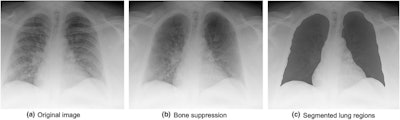

Since it can be difficult to interpret portable chest x-ray images of patients with COVID-19 -- because bone components overlap with the abnormal patterns of the disease -- the group used a bone-suppression technique during preprocessing of the images, testing the model with and without it.

Examples of images with bone suppression and manually segmented lung regions. Courtesy of the Journal of Medical Radiation Sciences.For distinguishing between death and recovery cases, the highest AUCs the model achieved were 0.756 and 0.959, depending on the number of radiomics features included. But its discriminative performance improved when the investigators used the bone-suppression technique, with a sensitivity of 90.9% and a specificity of 95.6% for predicting mortality or survival.